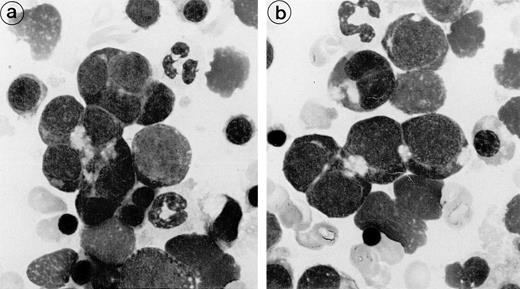

The erythroblastic synartesis could be reproduced in vitro: indeed, erythroblast cultures established with bone marrow progenitors from cases 2 and 3 displayed similar morphological abnormalities to those observed in vivo (Fig4a, see page 3686). Crossed culture experiments using the patient erythroblasts grown in the presence of their own serum or of a control serum, or using erythroblasts of a control subject grown in the presence of the patient sera (see Table1) were performed and gave the following results: the erythroblast abnormalities reproduced in culture in the presence of autologous serum were absent when the culture was performed with a control AB serum (Fig 4b). Electron microscopy confirmed these findings, showing that the same intercellular junctions were observed when the patient erythroblastic progenitors were cultured with autologous serum, but that they were absent when the culture was performed in the presence of a control serum. These abnormalities were not reproduced in vitro when the erythroblasts were grown in the patient sera that had been IgG depleted. This allowed us to conclude that the synartesis was caused by an IgG component. Further confirmation was given by the observation that cultured normal erythroblasts displayed authentic synartesis when grown in the presence of patient to serum. Finally, the IgG fractions from the patients were added to normal serum at a concentration of 2 g/L and were able to induce typical synartesis on control erythroblasts grown in this preparation (Fig 5).

Fig. 4.

Light microscopical aspect of the erythroblasts cultured from patient 2 bone marrow. (a) In the presence of autologous serum: The erythroblasts are closely apposed to each other with occasional nonbasophilic areas present at their junction, mimicking the morphology of the bone marrow smears. (b) In the presence of a control serum: The grown erythroblasts are scattered and individually disposed on this cytospun preparation and do not display the characteristic abnormalities of the disease.

Close modal